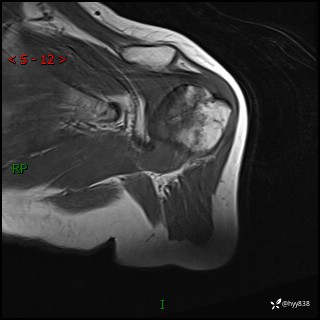

肱骨MRI平扫(axi T1WI+cor T2WI-fs)+CE-fs(COR+SAG)